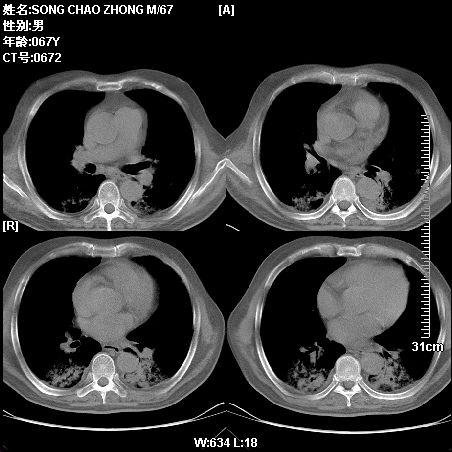

肿瘤科住院病人,都有食管癌史,都有放化疗治疗,两下肺病变是转移灶?还是其他原因造成?请老师指点

病例二 食管癌4个月,咳嗽咳痰,呼吸困难